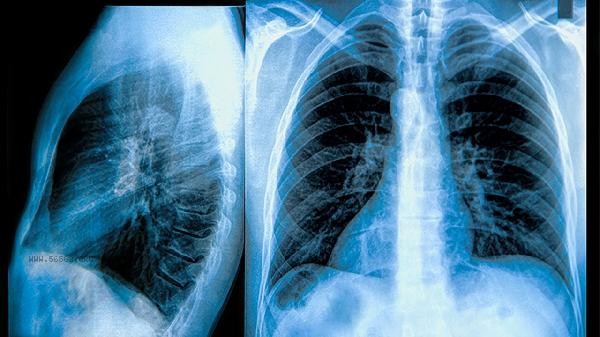

Patients with chronic obstructive pulmonary disease (COPD) can generally undergo pulmonary function tests, but they should be postponed during acute attacks or when there is severe respiratory distress. Pulmonary function examination is an important method for evaluating the condition of chronic obstructive pulmonary disease, which can help doctors determine the degree of airflow limitation and disease staging. Pulmonary function testing is of great clinical significance for stable COPD patients. The degree of airflow limitation can be determined by the ratio of forced expiratory volume to forced vital capacity in the first second, and bronchial dilation test can help identify diseases such as asthma. Before the examination, it is necessary to stop using short acting bronchodilators, avoid vigorous exercise, and cooperate with the technician to complete deep inhalation, explosive exhalation, and other actions. The examination results can guide medication adjustments, such as increasing the use of long-acting bronchodilators. When patients are in the acute exacerbation phase and show significant wheezing and decreased blood oxygen saturation, forced lung function tests may exacerbate respiratory distress. Patients with severe pulmonary hypertension, recent myocardial infarction, or hemoptysis should also be cautious. In such cases, the condition should be evaluated through blood routine, arterial blood gas, etc., and lung function tests should be considered after symptoms are controlled. When some severe patients are unable to complete standard testing procedures, a simplified examination plan can be used. Patients with chronic obstructive pulmonary disease (COPD) should adhere to medication and regularly check their lung function. It is recommended to undergo testing at least once a year. Mild dizziness after examination is a normal phenomenon, which can be relieved after rest. If chest pain or severe coughing occurs during the examination, it should be terminated immediately. Pay attention to avoiding smoking and respiratory infections in daily life, and perform lip tightening breathing training to improve lung function.